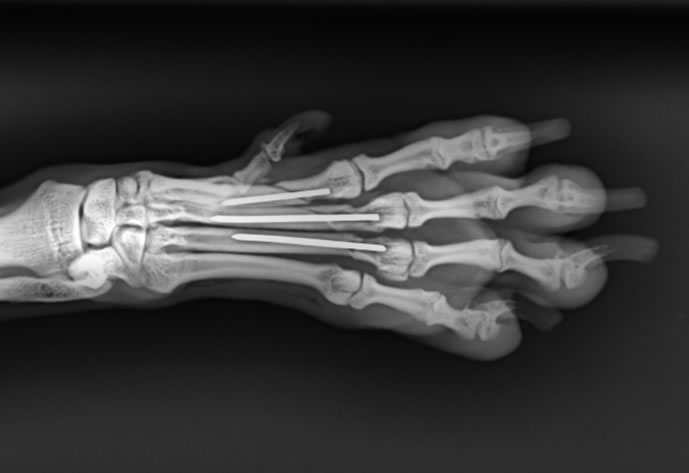

結合影像學、理學檢查與運動力學,提出適合的骨科治療方案

也許是車禍、也許是玩樂時不小就跛腳了,究竟只是扭傷,還是骨折脫臼?需要正確的X光診斷,判斷傷勢,再結合運動力學,規劃合適的骨科手術方案,避免只吃止痛藥造成永久性的傷害,再配合術後正確的照顧與復健,讓毛小孩重獲行動的自由。